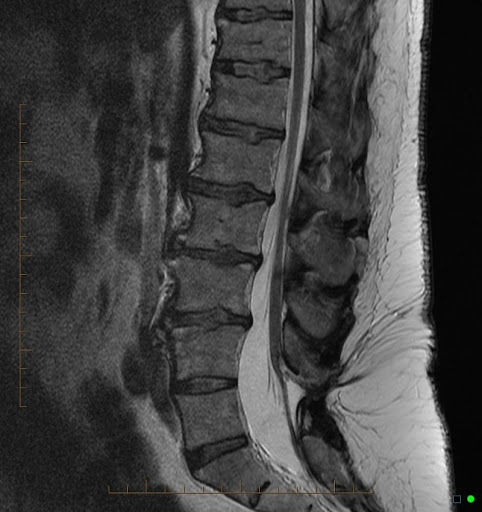

spinal imaging

T1: CSF dark, pathology often dark

T2: CSF bright, pathology often bright

STIR (short tau inversion recovery): T2 with suppression of fat